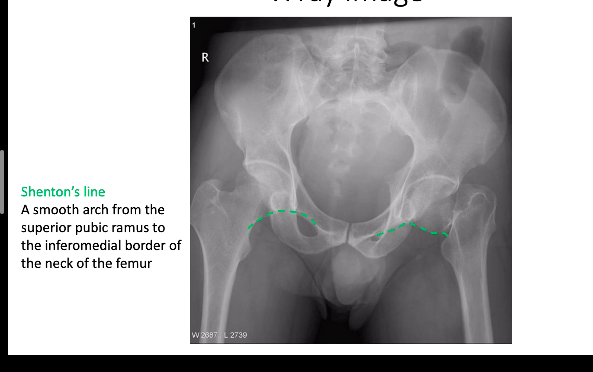

what do we use to look at aligment of the hip?

shentons line: smooth arch from the superior pubic ramus to the inferomedial border of the neck of the femur